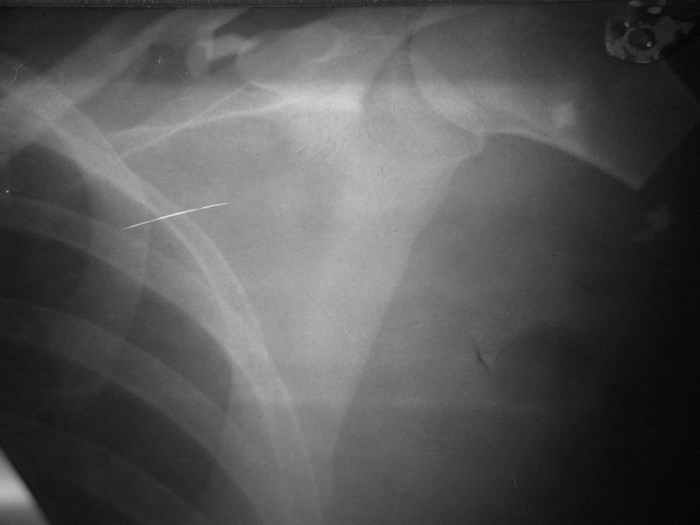

Убольной З. 26 лет, пострадавшей в результате ДТП имеетсз травматический отрыв левой верхней конечности на уровне проксимального отдела плечевой кости. В ургентном порздке (08.08.05) произведена ПХО раны с формированием культи конечности. В настозщее времз заживление полное. Имеютсз фантомные боли, приемущественно во вторрой половине днз. Фоторентгенограмма прилагаетсз.